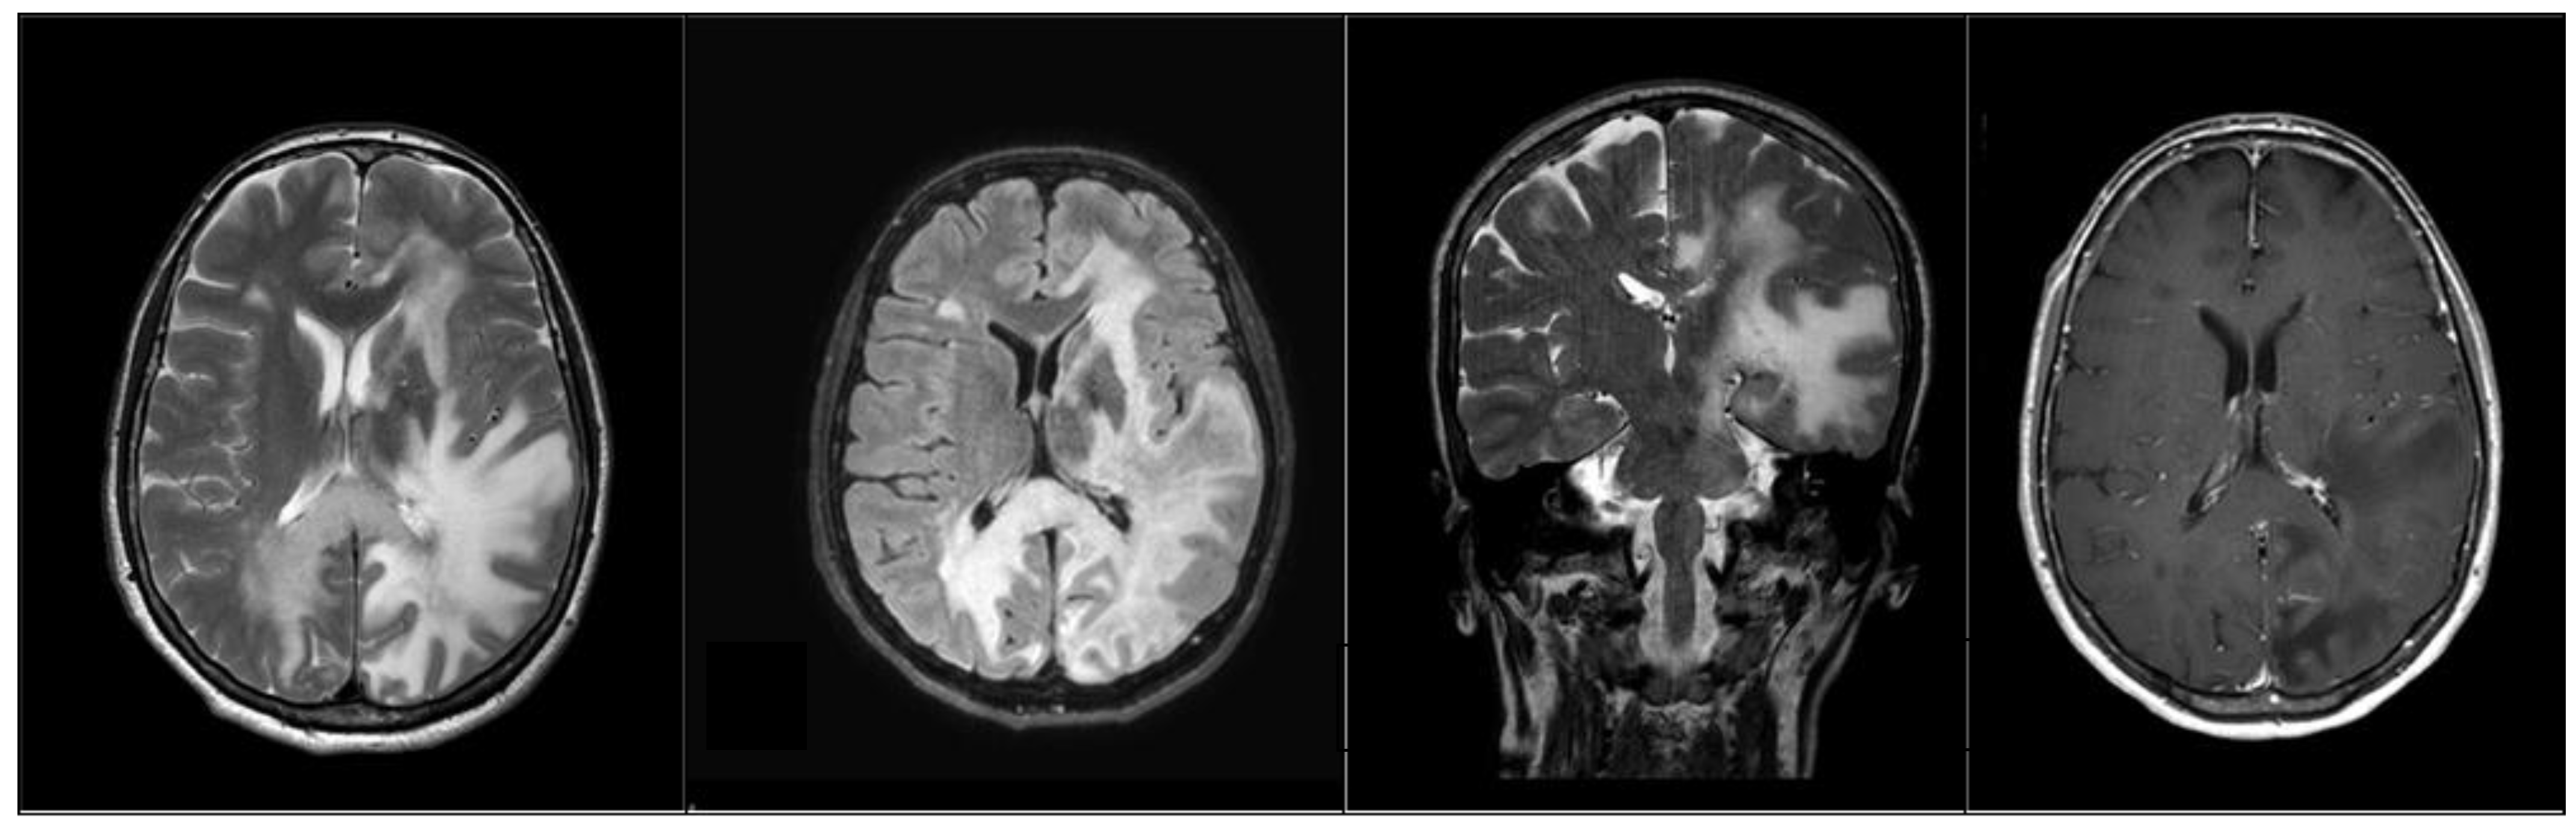

2. Case Presentation